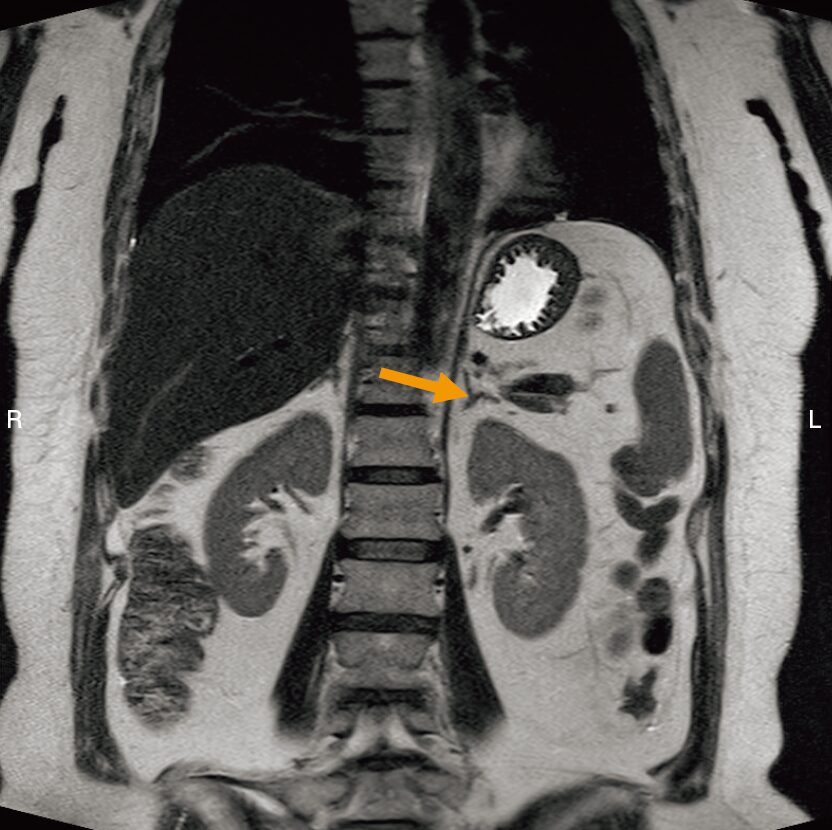

腹部 MRI の T2 強調像を示す。 矢印で示すのはどれか。

3.左副腎

- まず、画像右側(患者さんの左側)にある「左腎臓」を見つけます。(そら豆のような形)

- そのすぐ内側(背骨寄り)かつ頭側を見ます。

- そこに、「Yの字(または三角形)」をした小さな構造物がありませんか?

- それが「左副腎」です!

- 左副腎の目印は、左腎臓の内側上部にある「Yの字(三角形)」。

- 右副腎は、IVCの後ろにある「線状」の構造。